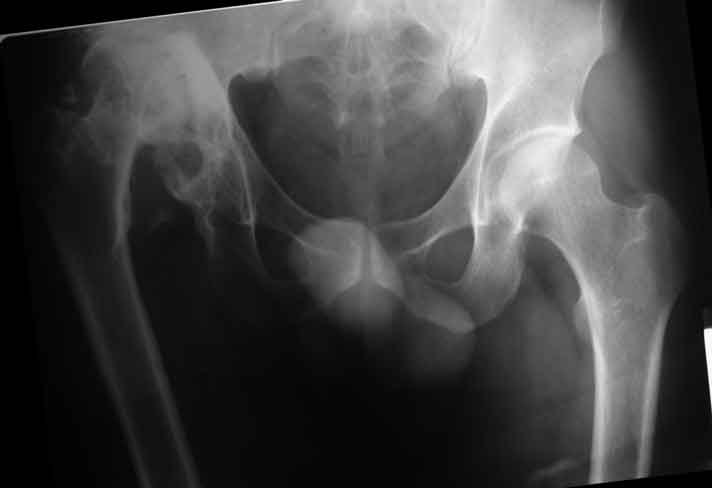

Уважаемые коллеги, пациент 30 лет, 4 года назад попал под поезд, ампутация обеих голеней в в/3, подвздошный вывих бедра (теперь застарелый). несмотря на такую ситуацию, пациент вполне прилично ходит и объем движений в неоартрозе близок к неповрежденной стороне. Основная жалоба - боль при нагрузке и в покое. Планируем двухэтапное лечение: резекция шейки, мобилизация проксимального отдела бедра, низведение бедра АВФ, вторым этапом б/ц эндопротезирование. Как поступить с головкой, вроде бы при протезировании можно будет обойтись без пластики, или ошибаюсь? Оставить ее там, где она есть? Другие варианты лечения.